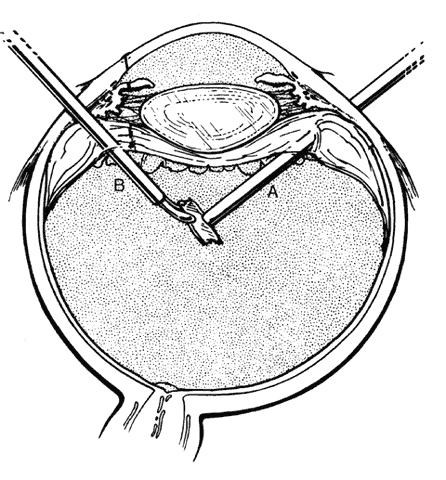

The vitreous cortex posterior to the equator is removed, if possible, from eyes with intraretinal foreign bodies. If not detached spontaneously, it is separated with a retinal pick (Fig. 14) or by suction with a soft-tipped cannula. The retinal laceration at the site of foreign-body incarceration is surrounded by laser and supported by a localized scleral buckle when the surrounding cortical vitreous cannot be removed. If present, subretinal fluid surrounding the incarceration site is drained internally through the retinal laceration while a fluid-air exchange is performed. Endolaser is applied around the break and the air is replaced by a short-acting gas tamponade.

Fig. 14. Creation of posterior vitreous detachment by a vit-reoretinal pick (gentle aspiration with soft-tipped cannula is an alternative). (Sternberg P: Trauma: Principles and techniques of treatment. In Ryan SJ (ed): Retina, Vol 3, p 484. St. Louis, CV Mosby, 1989)A